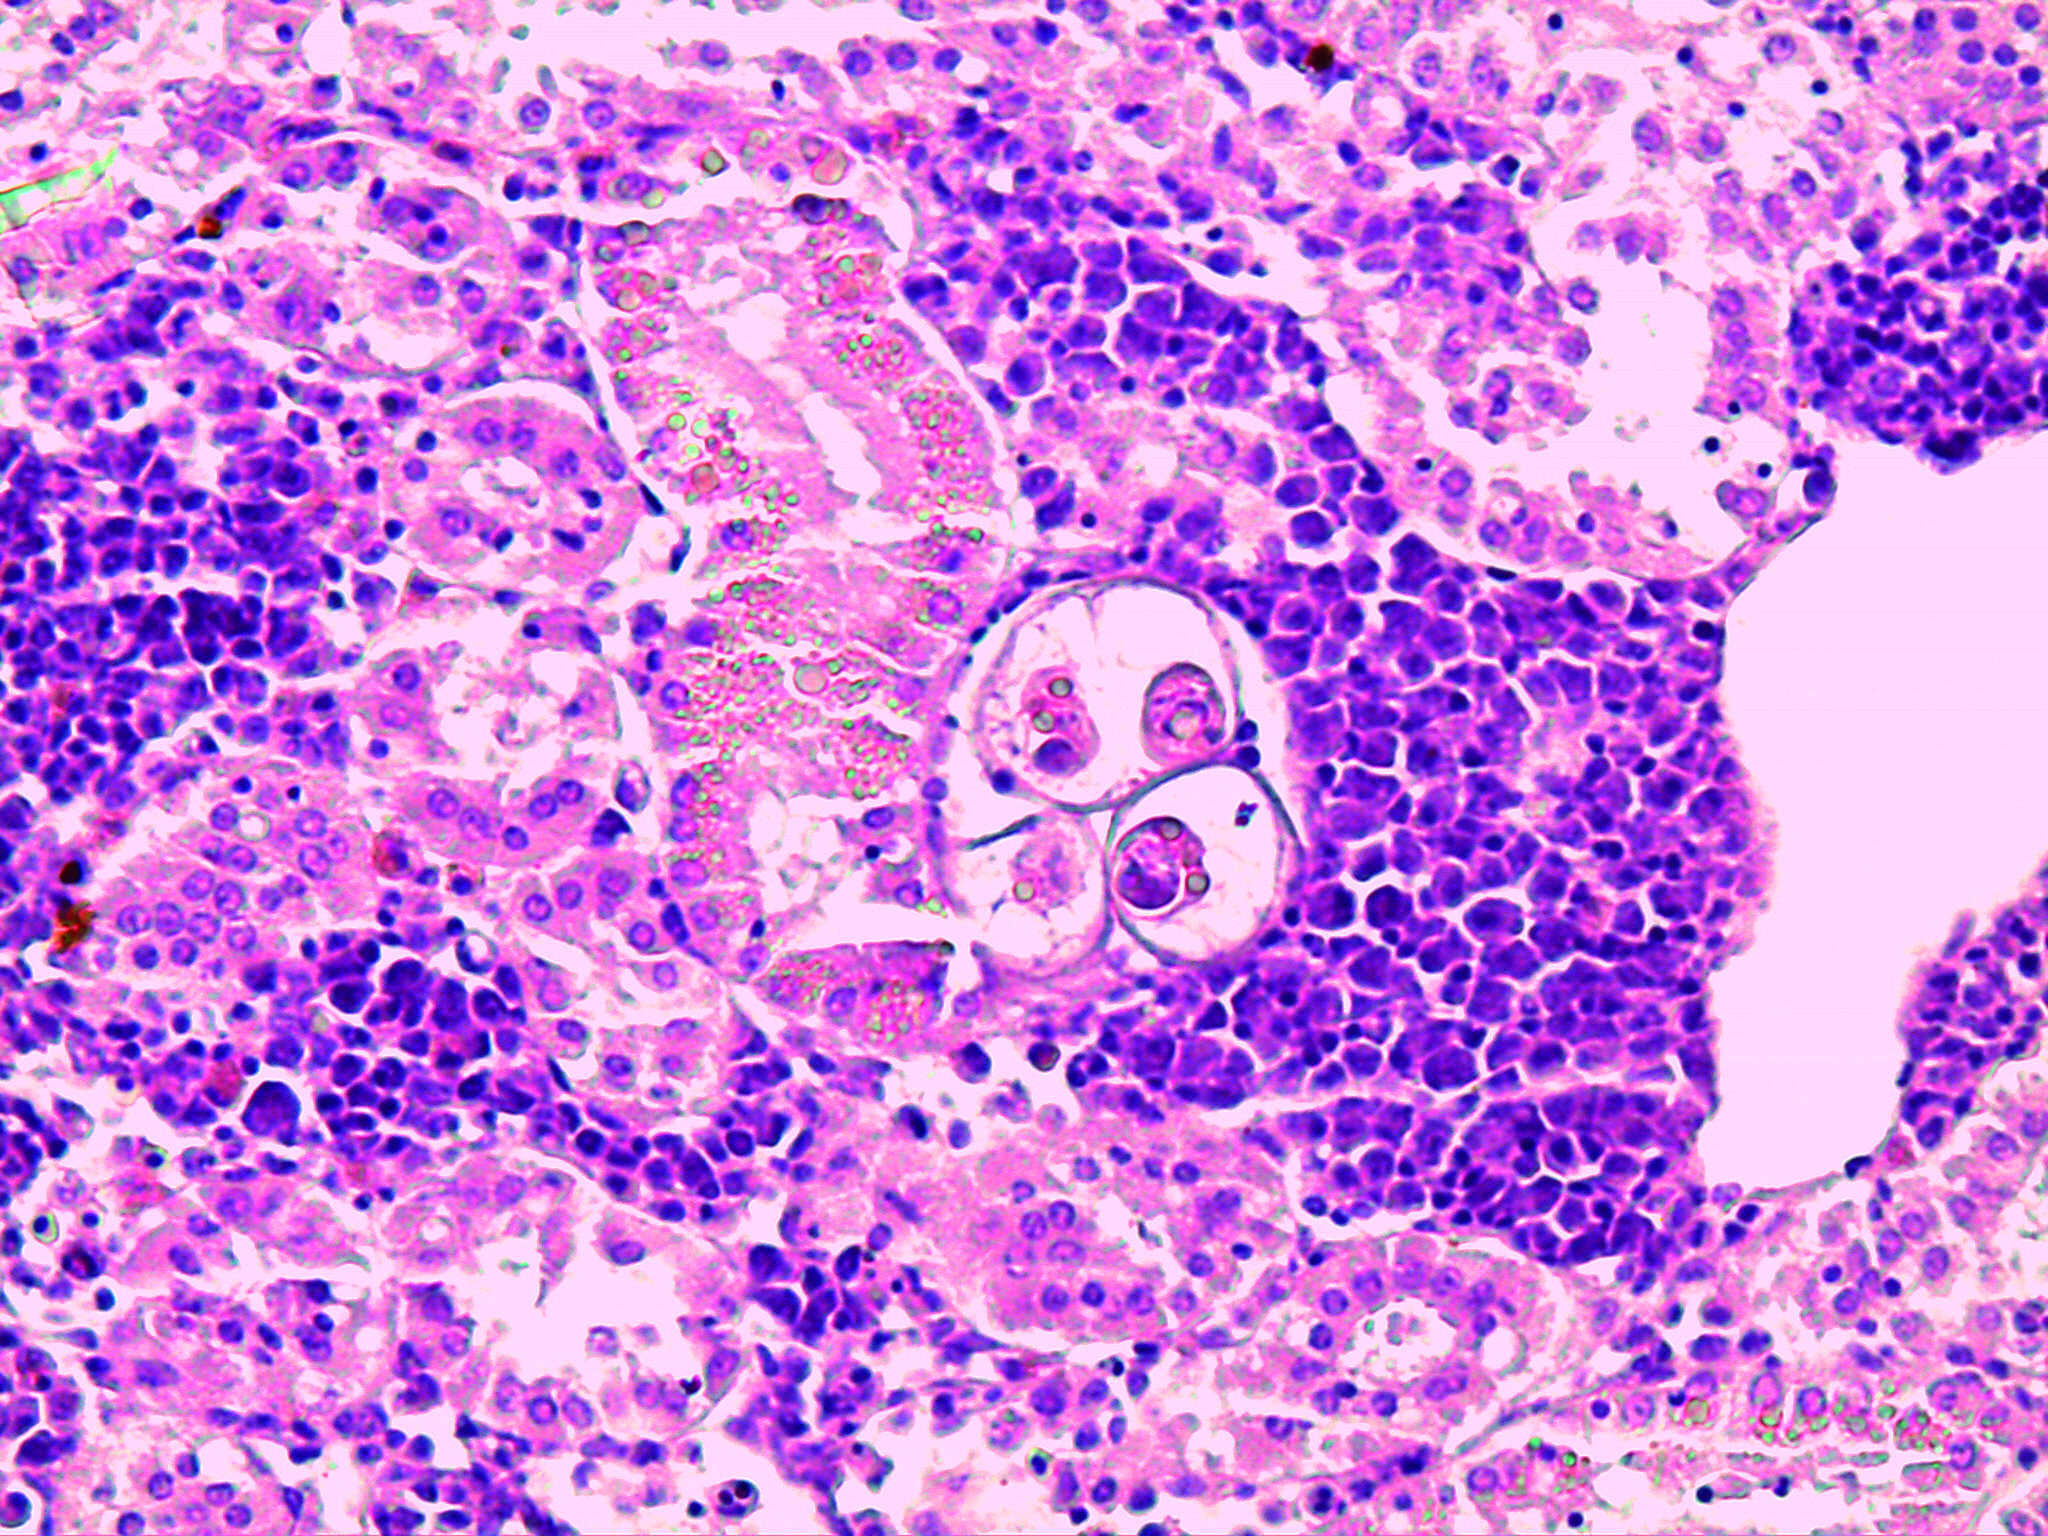

Enteromyxosis

Agent: Enteromyxum leei (Myxidiidae, Myxozoan histozoic parasite).

Symptoms: This Myxosporean parasite infects the intestinal mucosa of gilthead sea bream causing severe weight loss and high mortality. Sea bass may act as a carrier without being affected. Horizontal transmission occurs between fish via pre-sporogonic forms expelled in fecal packets, rather than spores typical of other myxosporeans. Mature spores have a characteristic “croissant” shape with polar capsules at their ends.

Control: No treatment. Prevention involves separating fish of different sizes to reduce transmission, net cleaning and removal of mortalities.